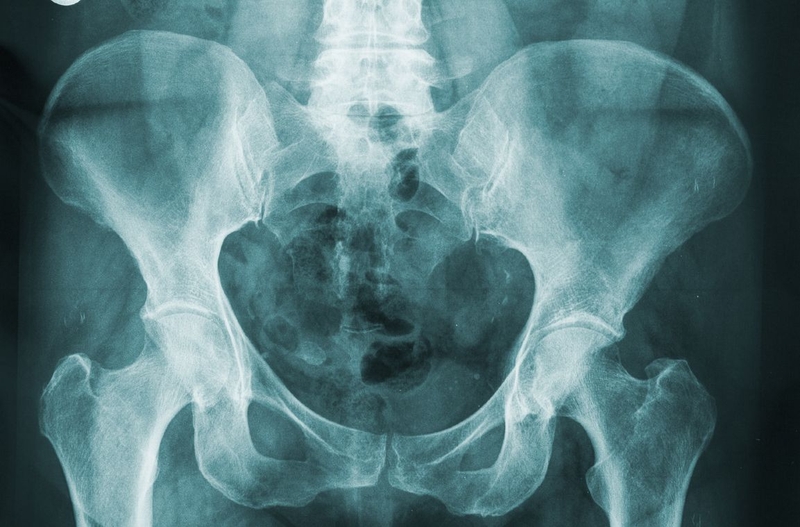

Khung chậu của con người có chức năng như một chiếc giá đỡ, bảo vệ các tạng như trực tràng, buồng trứng, tử cung, bàng quang… Khung chậu có cấu tạo gồm 4 xương là 2 xương chậu, xương cùng trên và xương cụt dưới. Xương chậu là xương to, dẹt, hình cánh quạt. Xương cùng gồm 5 đốt, đỉnh xương cùng tiếp giáp với xương cụt. Xương cụt gồm 4 - 6 đốt, có một mặt trước, 1 mặt sau và 2 bờ.

Các xương của khung chậu được kết nối với nhau bằng 4 khớp bán động gồm: khớp mu, khớp cùng - chậu, khớp cùng cụt. Ở nữ giới, các khớp này có khả năng giãn nở trong quá trình phụ nữ chuyển dạ. Điều đặc biệt này giúp đầu thai nhi có thể chui qua khung chậu. Khi thai phụ càng lớn tuổi hoặc càng ít vận động, khả năng giãn nở của khung chậu càng giảm.

Máy chụp X quang phát ra các chùm tia X. Tia X đi xuyên qua vùng khung chậu và hình ảnh khung chậu sẽ được thu lại, hiển thị trên phim. Do xương có khả năng cản tia X nên trên phim X quang xương sẽ có màu trắng. Những mảng tối, xám hơn chính là các mô, cơ khác xung quanh xương.